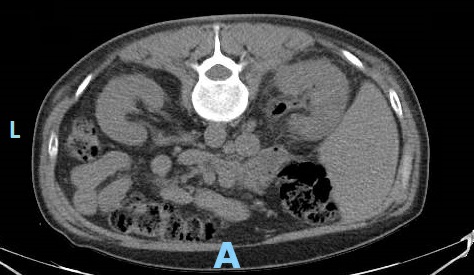

Case Presentation: A 50 year old man with poorly controlled type 2 diabetes mellitus (DM) presented with flank pain, nausea, vomiting, and fever. On exam, he was febrile, tachycardic, hypotensive, and had right sided CVA tenderness. The ER performed a CT stone protocol, however, imaging demonstrated right sided emphysematous pyelonephritis (EPN). Our patient was admitted with severe sepsis, pre-renal acute kidney injury, hyponatremia, and hyperglycemia. Piperacillin/Tazobactam was started, appropriate IV fluid resuscitation was administered, and urology was consulted. Urology recommended placement of both a Foley catheter and percutaneous nephrostomy tube for maximal drainage, even though there were no signs of obstruction. Interim lab work demonstrated a hemoglobin A1c of 16%, increased from 12%. Three days later, despite stable blood pressures and blood and urine cultures demonstrating antibiotic sensitive E. coli, he continued to have a rising leukocytosis, tachycardia, and severe pain. Repeat CT abdomen/pelvis with contrast showed new areas of necrosis and new abscesses in the anterior and lower pole of the right kidney and retroperitoneum. He was taken to the OR for emergent nephrectomy. His course was further complicated by IVC injury and hemorrhagic shock requiring massive transfusion. Subsequent anasarca precluded closure of his abdominal incision and he was monitored in the SICU. He returned to the OR six days later for closure and was discharged home after receiving insulin teaching and DM education.

Discussion: This case highlights the importance of diabetes management in prevention of EPN. Over 80% of patients with EPN have concurrent DM. Our patient’s only risk factor was DM; he had no evidence of obstructive uropathy, was not over age 60, and was not of female sex. Hyperglycemia and glucosuria provide favorable conditions for gas forming pathogens to cause severe infection. DM related autonomic neuropathy results in incomplete emptying of the bladder, further increasing the risk of ascending urinary tract infection. In vitro studies also demonstrate that humoral immunity and neutrophil function are impaired in diabetic patients. This is likely why our patient did not appear clinically worse despite the formation of new abscesses.Management of EPN consists of antibiotic administration and drainage by percutaneous nephrostomy. If these measures are insufficient, total nephrectomy is necessary. CT scan provides prompt diagnosis and staging so appropriate treatment is initiated to preserve renal function and prevent clinical deterioration. CT should be repeated within 3 days if there is concern for worsening infection. Although cases of EPN are fairly rare, its strong association with DM supports the need for optimal glycemic control in our diabetic patients. Additionally, a lower threshold for repeat imaging and escalation of care is warranted in these patients due to their impaired inflammatory response.